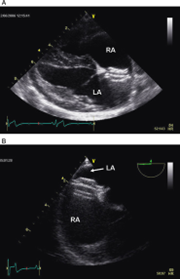

Echocardiographic findings

Echocardiography serves as the cornerstone for diagnosing and characterising PS (Figure 1). Typical echocardiographic findings include thickening and reduced mobility of the pulmonary valve leaflets for valvular stenosis. In mixed-type presentations, narrowing of the pulmonary valve annulus or pre/supravalvular obstructions, consisting of fibrotic tissue, are common. Post-stenotic dilation of the pulmonary artery is common due to the faster flow across the valve region. Doppler interrogation allows for the quantification of the PG across the stenotic segment, aiding in disease severity assessment.

Secondary changes include reduced right systolic function, right ventricular hypertrophy and right atrial enlargement with/without tricuspid regurgitation. Signs of right-sided congestive heart failure (CHF) include ascites and pleural or pericardial effusion.